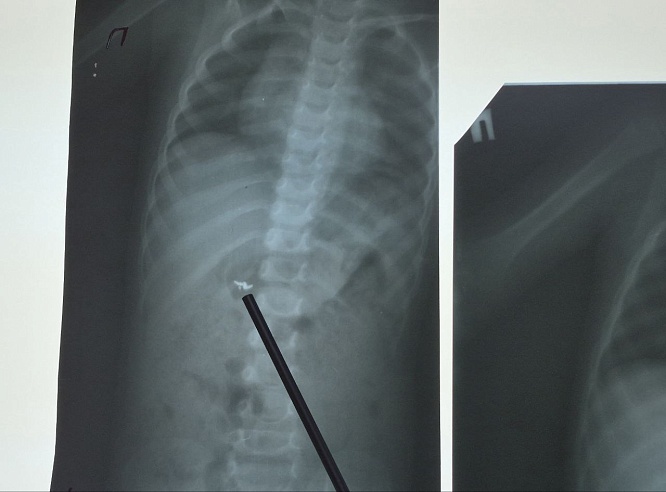

В Хвалынской больнице был сделан рентгеновский снимок - инородное тело находилось в желудке. Малыша перенаправили в Балаково. Контрольный снимок показал, что инородное тело состоит из трех частей и находятся они уже не в желудке, а распределились по кишечнику.

"Ребенок вместе с мамой госпитализирован. Он находится под наблюдением врачей. Прогноз благоприятный. Однако, до выхода частей цепочки естественным путем, малыш будет оставаться в стационаре", - рассказали в Балаковской клинической больнице.